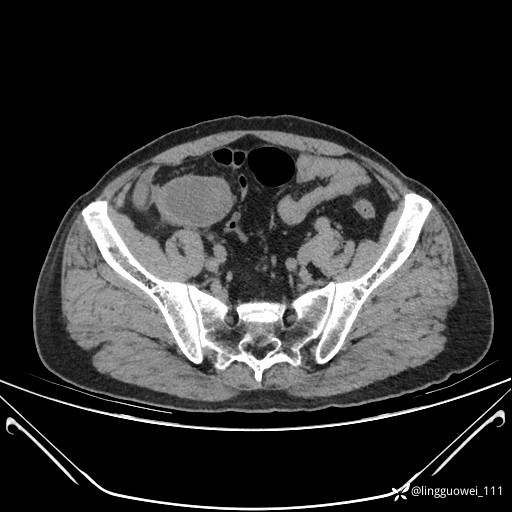

62岁,男,2天前无明显诱因出现下腹部疼痛不适,呈持续性,程度稍剧,同时伴有尿频、尿急及尿不尽感,无畏寒、发热。

平扫: